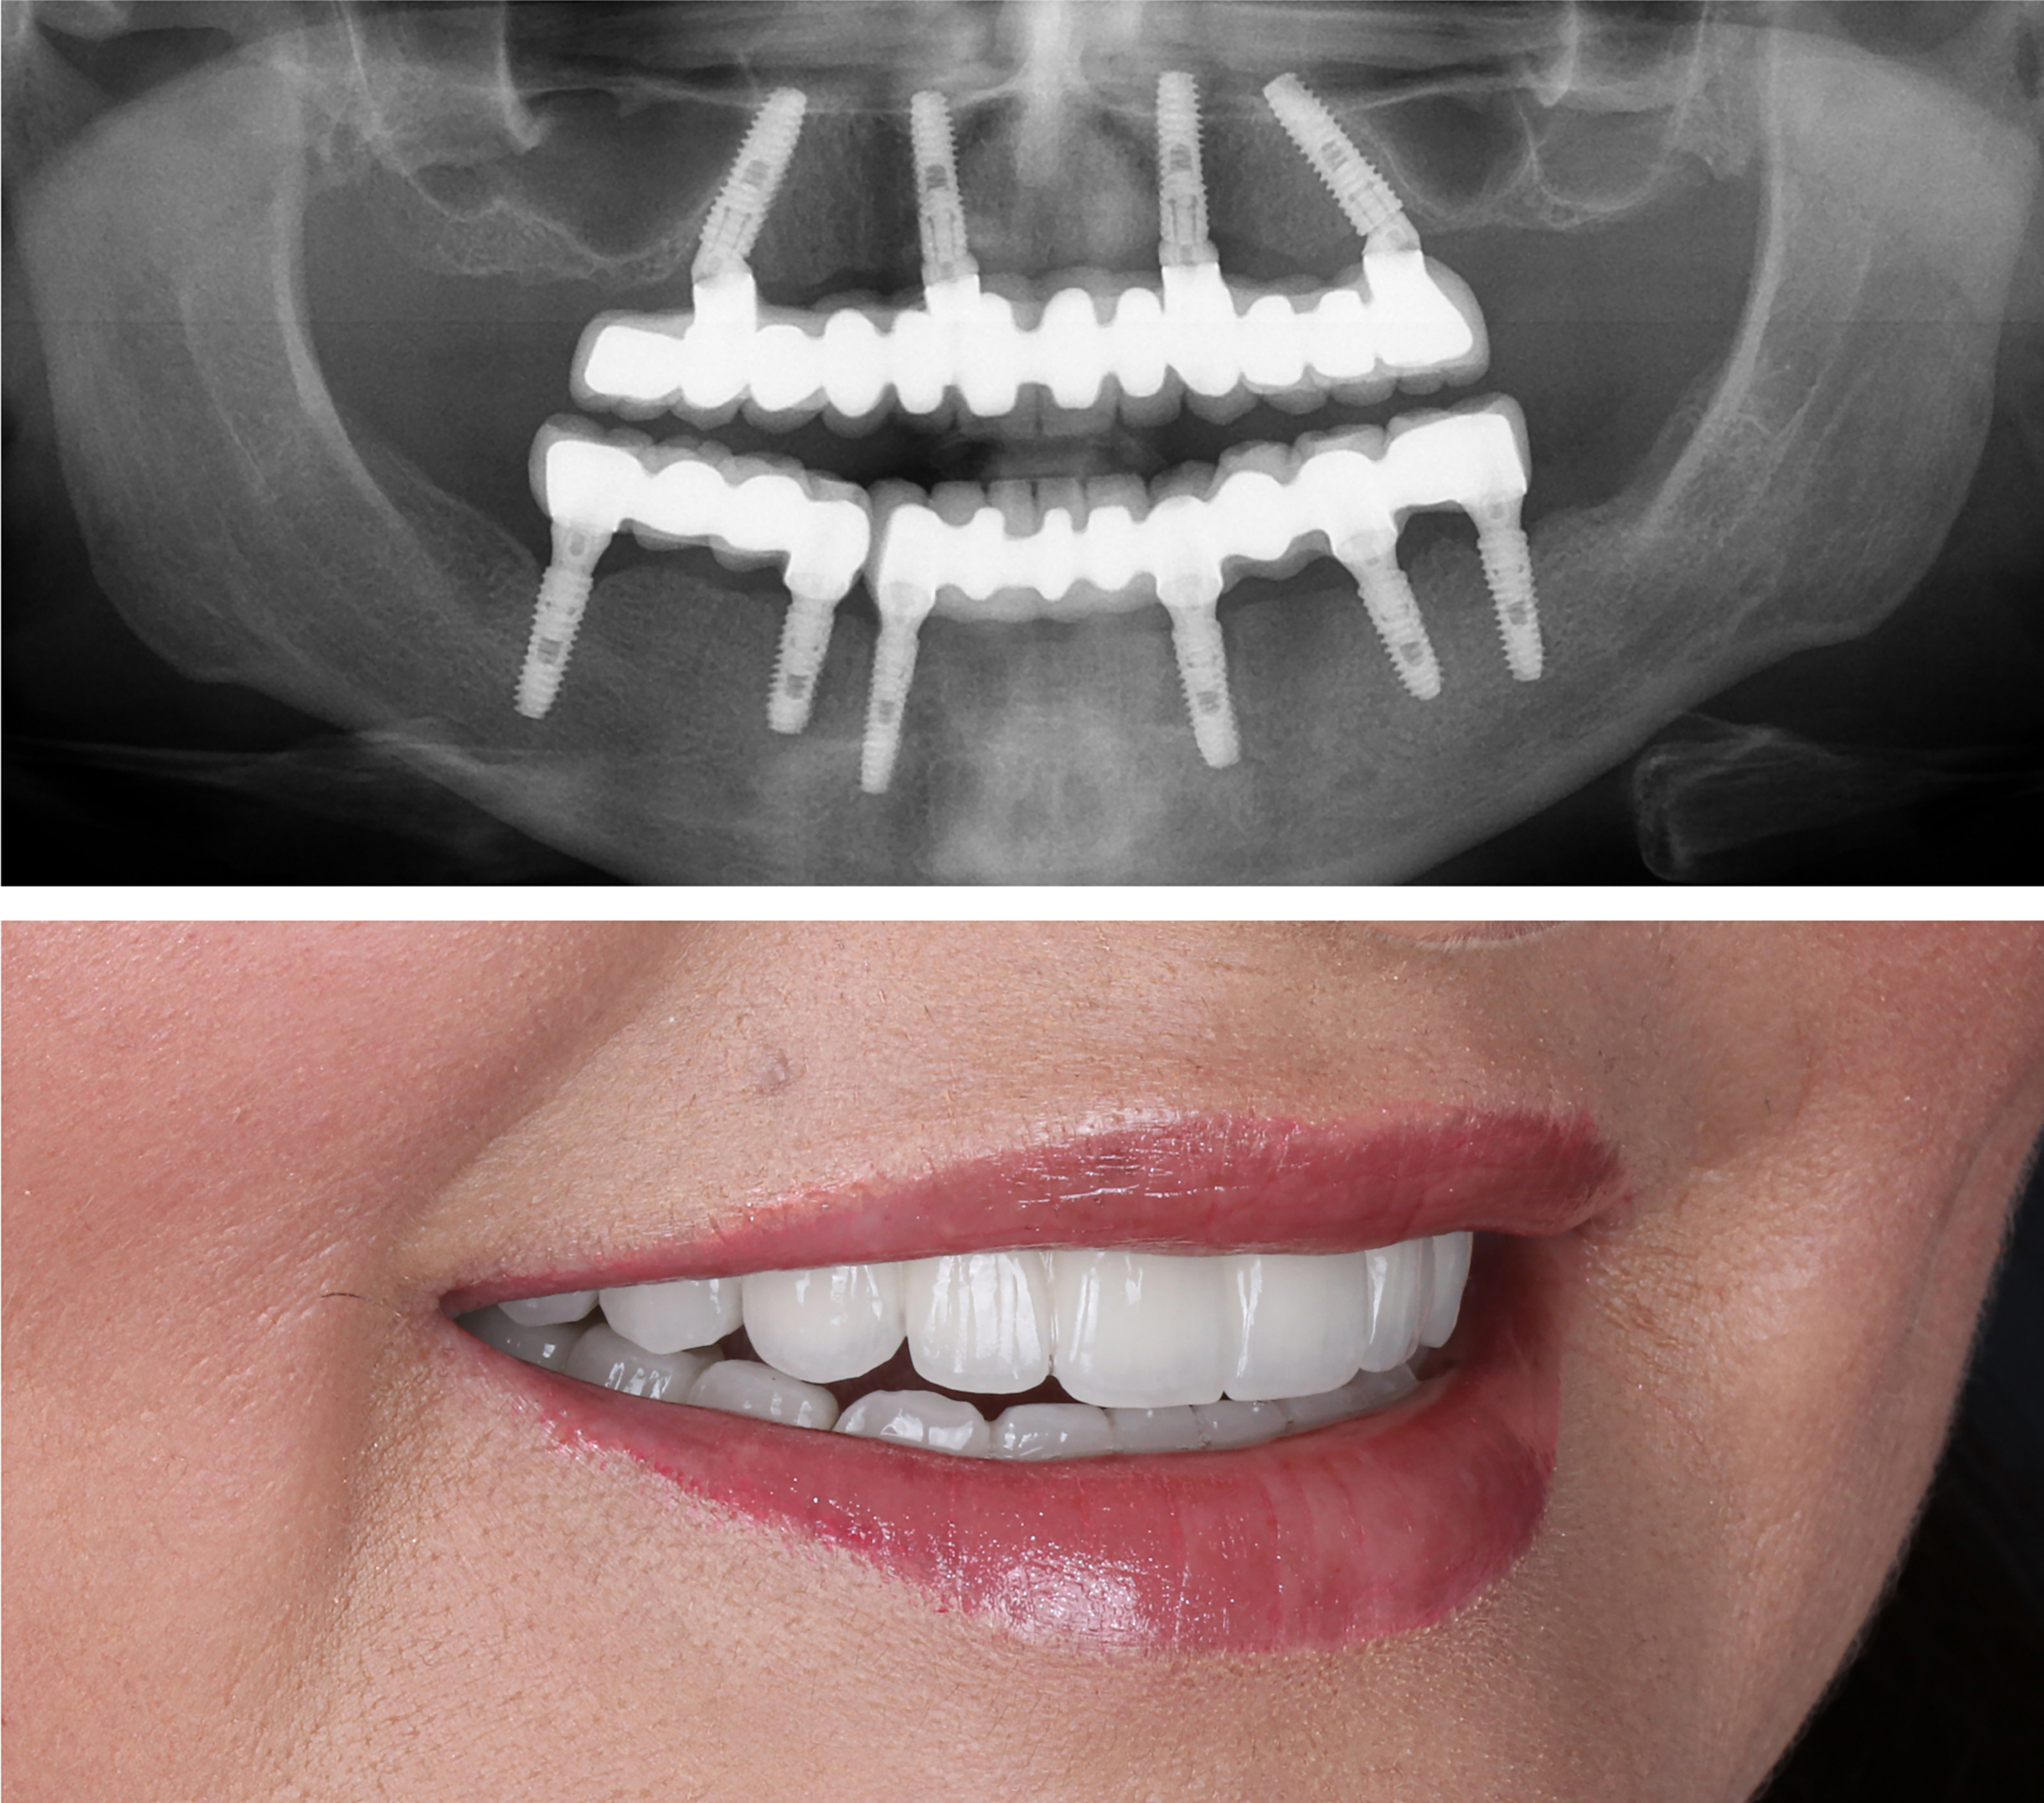

Example transformations achievable with dental implants

These images are for illustrative purposes only and do not represent actual patients treated at Karimi Dental.